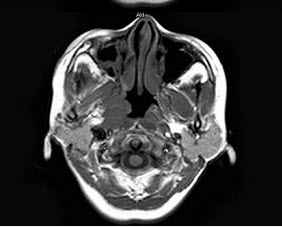

女,34岁。右侧听力下降,耳鸣2个月。MRI平扫及增强扫描如图示,最可能的诊断是()。

A、鼻咽癌

B、脑膜瘤

C、神经源性肿瘤

D、动脉瘤

E、未见异常

正确答案:

A